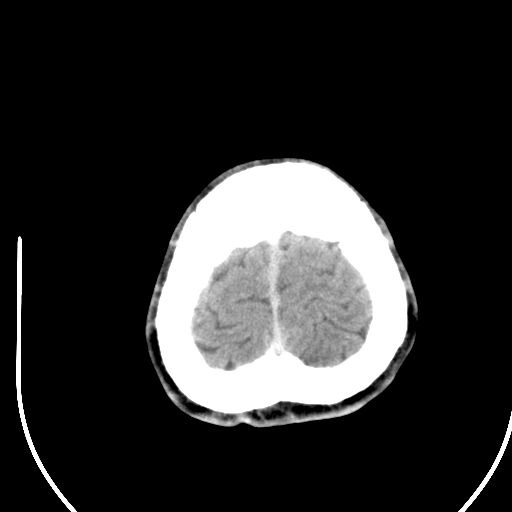

标题: CT28158:男,27Y。头痛数月,左顶叶血管瘤。 [打印本页]

标题: CT28158:男,27Y。头痛数月,左顶叶血管瘤。